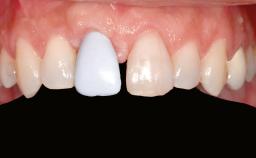

Shell Technique for Horizontal and Vertical Maxillary Bone Augmentation in a Partially Edentulous Patient with Aggressive Periodontal Disease

Prosthesis Type FDP

Defining Characteristics Up to three missing teeth to be replaced with an implant-borne restoration or restorations

Mesio-Distal Space Anatomic space corresponding to the missing teeth +/- 1 mm

Inter-Arch Distance > 8 mm